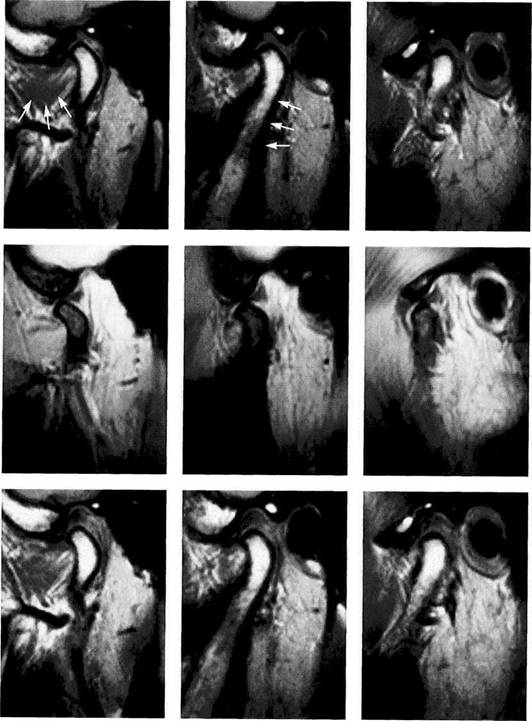

For an examination of the temporomandibular joint the practitioner does not need all the MRI slices that have been prepared and stored in the computer. Three layers-a lateral, central, and medial-for each mandibular position are com­pletely adequate. One should be able to make an unequivo­cal evaluation of the fossa, disk, and condyle on each slice. In addition to the Tl-weighted scan in habitual occlusion and the T2-weighted scan at maximum jaw opening, a Tl-weighted scan in the prospective therapeutic mandibular position should always be made if there is a suspected disk displacement with repositioning.

In the past, the therapeutic disk position was determined through clinical measures alone (Owen 1984, Davies and Gray 1997a-c) or with the help of electronic axiography. According to recent studies (Kircos et al. 1987, Katzberg et al. 1996), joints that are free of clicking sounds do not necessarily have a normal disk position. Therefore an image of the "therapeutic" disk-condyle relation is important for planning the treatment. The importance of this procedure is directly proportional to the complexity of the definitive occlusal stabilization that will be required after disk reposi­tioning.

Habitual occlusion

MRI exposures at habitual occlusion are always made in a T1-weighting with the so-called spin-echo (SE) technique. The radiologist usually exposes six to eight slices, although images of only three layers (medial, central, and lateral) are necessary to adequately evaluate the disk-condyle relationship (Crowley et al. 1996). In a medial slice the lateral pterygoid muscle (arrows) can be identified. In the central slice (cen­ter) the posterior border of the as­cending ramus (arrows) is always visible.

Maximal jaw opening

The second obligatory joint series is made at maximal jaw opening in T2-weighting. The T2-weighting is well suited to reveal inflammatory reactions and joint effusions (Larheim 1995). The combination of exposures (Tl closed and T2 open) makes it possible to avoid a complete MRI series with both weightings. Again, a lateral, cen­tral, and medial slice are made. If the maximal jaw opening is not se­cure, false positive findings are like­ly to be made (Watt-Smith et al.

Therapeutic occlusion

The most important sequence of the MRI examination is the depic­tion of the positional relationships of the fossa, disk, and condyle in the treatment position of the mandible. The prognosis of a con­servative repositioning treatment depends to a large extent upon this view. To demonstrate a complete repositioning, medial, central, and lateral slices must again be made. When there is disk displacement without repositioning, this view is not as suitable as one in an angled coronal plane.